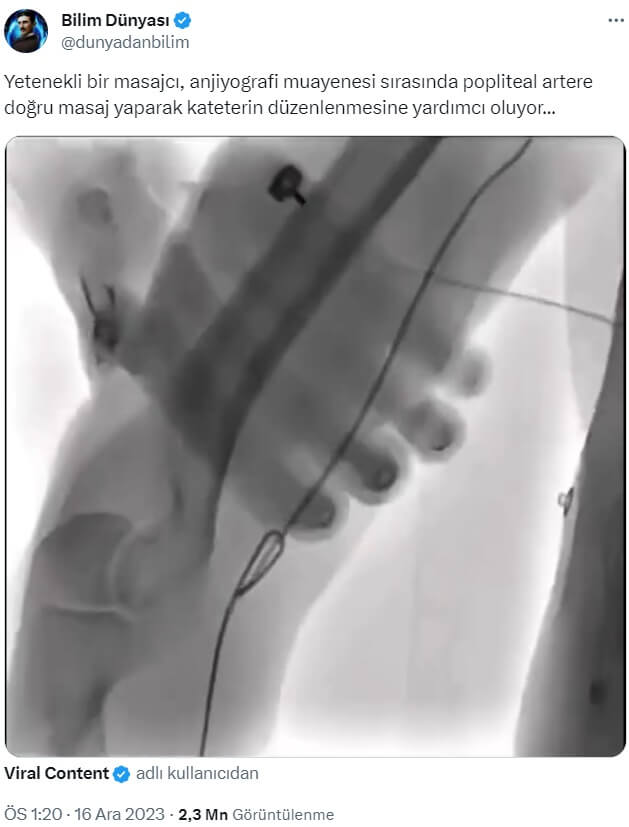

“A skilled massager helps in the regulation of the catheter during an angiography examination by massaging right in the popliteal artery.” (“Yetenekli bir masajcı, anjiyografi muayenesi sırasında doğrudan popliteal artere masaj yaparak kateterin düzenlenmesine yardımcı oluyor.”) cümlesini barındıran söz konusu video şu şekilde:

Anjiyo prosedüründe damar erişiminde kritik rol oynayan dışardan manevra görüntüsü 2023 yılı Aralık ayında Bilim (!) Dünyası ve Gusholder Haber Bülteni gibi hesaplar tarafından “Yetenekli bir masajcı, anjiyografi muayenesi sırasında popliteal artere doğru masaj yaparak kateterin düzenlenmesine yardımcı oluyor…” ifadeleriyle paylaşıldı.

“Masajın gerçekliği: Sağ bacak içindeki popliteal arterin el ile düzeldiği an“ ifadeleriyle paylaşılan videoda, anjiyografi esnasında damar içine yerleştirilen “kılavuz tel”in (“guidewire”) / “kateter”in arter içinde kıvrıldıktan sonra yapılan müdahale ile düzeltildiği an görülüyor (Danıştığımız doktorlar görülen cismin kateter değil kılavuz tel olduğunu aktardı).

- Femur, tibia, fibula ve patella gibi kemiklerin görülmediği video bacak değil dirsek eklemine müdahale içeriyor.

- Popliteal değil brakial ya da radial arter.

- Müdahale masajcı değil kardiyolog ya da anjiyografiye katılan bir sağlık çalışanı tarafından yapılıyor.

- Anjiyografi esnasında kateter veya kılavuz tel ilerletilip çekilirken bu tip manevralar yapılır.

Bir damar kardiyologunun bükülmüş kılavuz teli / kateteri düzeltmek için hastanın dirseğine eliyle baskı yaptığı hamle bir uzman tarafından şöyle yorumlandı:

Prof. Dr. Mehmet Kadri Akboğa görüntü hakkında “Bacak veya kalp damarları için anjiyo yaptığımızda diz veya dirsek bölgesinde kıvrıntılı kısımlardan geçebilmek için bazen dışardan manevralar yaparak damarı düzleştirmemiz gerekiyor❤️” ve “oysa kateter laboratuvarında masajcı ne arar, operatör kendisi steril olarak örtü üzerinden yapıyor bu manevrayı” ifadelerini kullandı.

Prof. Dr. Güner Sönmez de görüntüyle ilgili paylaşımında “Bu doğru değil: 1. Damar değil, damar içinde katlanan kateter düzeltiliyor. 2. Bu bacak değil, kol.” dedi.